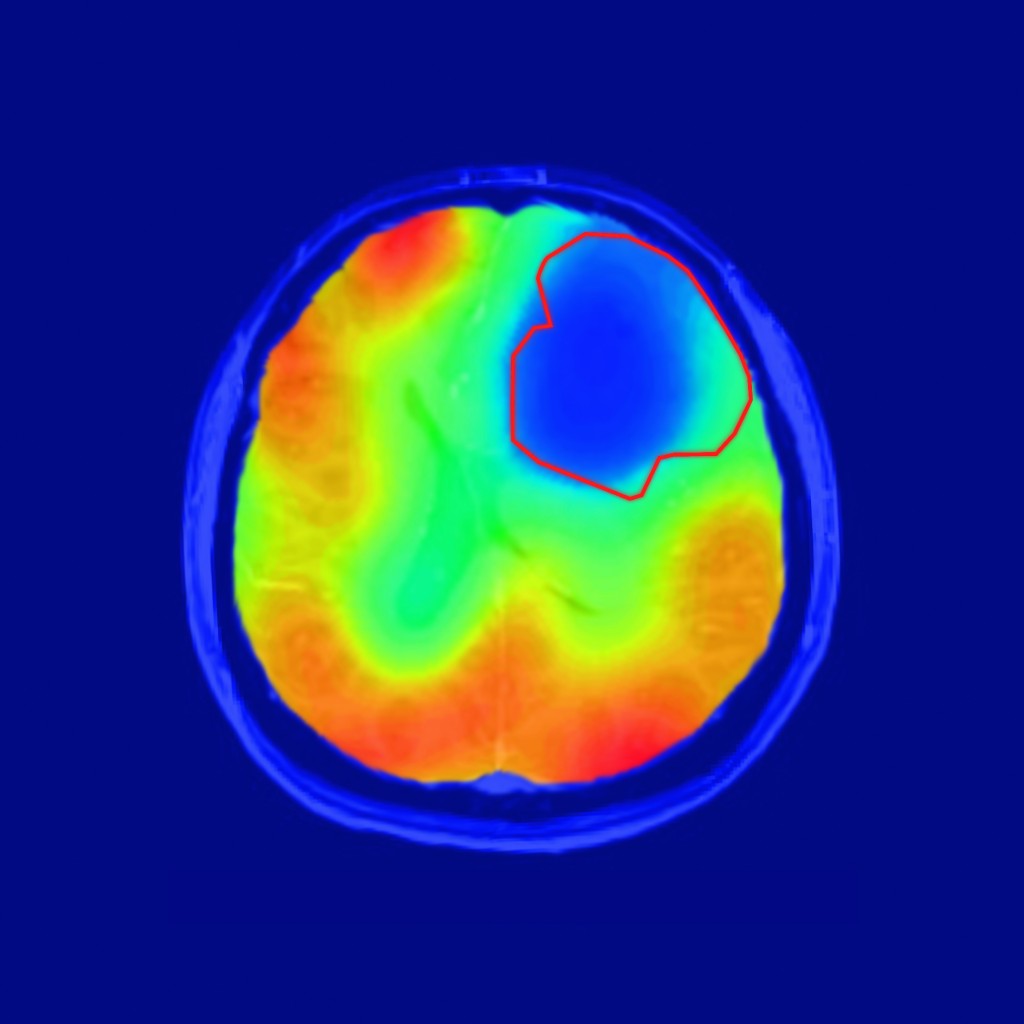

Selbst kleine Tumore im Gehirn lassen sich mit einer neuen Technik zuverlässig darstelle, die Deutschen Krebsforschungszentrum (DKFZ) in Heidelberg entwickelt worden ist. Als bildgebendes Gerät fungiert ein Magnetresonanztomograph (MRT). Die Patienten atmen, bevor sie in die Röhre geschoben werden, da Sauerstoffisotop 17O2 ein, das nicht radioaktiv ist und vom Körper gut vertragen wird. Überall, wo in den Körpergeweben Sauerstoff verbraucht wird, geht das Isotop eine Verbindung mit Wasserstoff ein. Dadurch wird es im Magnetfeld des MRT nachweisbar. Gewebe, das viel Sauerstoff umsetzt, erscheint daher im Bild hell. Bild: Paech / Radiology Tumorzellen mögen keinen Sauerstoff Tumorzellen bilden verstärkt Milchsäure. Diesen anaeroben, also ohne Sauerstoff auskommenden, Stoffwechsel hat der deutsche Arzt und Biochemiker Otto Heinrich Warburg bereits in den 1920er Jahren beobachtet. Gesundes Gewebe im Gehirn ist jedoch auf Sauerstoff angewiesen. Es entstehen Wasserstoffatome, die im MRT tanzen, wenn sie von Radiowellen angeregt werden, die stoßweise auftreten. Wenn sie abgeschaltet werden kehren die Wasserstoffatome in ihre Ausgangslage zurück. Dabei senden sie Signale aus, die von Detektoren aufgefangen werden. Daraus errechnet der Computer ein Bild. Tumoren erscheinen als dunkle Flecken Die DKFZ-Wissenschaftler um den Arzt und Physiker Daniel Paech und seinen Kollegen Sebastian Niesporek haben das Prinzip zunächst mit drei gesunden Probanden durchgespielt. Wie erwartet ließen deren Gehirne einen normalen Sauerstoffumsatz erkennen. Dann untersuchten die Forscher zehn Probanden, bei denen ein Gehirntumor diagnostiziert worden war, mit der neuen Technik. „Das Ergebnis war wirklich eindrücklich: Die Tumoren erschienen im Bild als dunkle Flecken, weil hier kein Stoffwechsel mit Sauerstoff stattfand“, so Paech. Eine vergleichbare Technologie existiert derzeit nur für die Positronen-Emissions-Tomographie, aber nur mit der radioaktiven Sauerstoffvariante 15O2 benötigt wird. Herstellung des Isotops ist langwierig und teuer Routinemäßig einsetzbar ist die Methode dennoch nicht. 17O2 ist sehr teuer, weil die Anreicherung sehr aufwändig ist. Paech geht jedoch davon aus, dass die Produktionskosten sinken, wenn das Molekül in größerem Maßstab hergestellt wird. Das Isotop im Sauerstoff der Luft in winzigen Mengen enthalten. Um es aufzukonzentrieren wendet die NUKEM Isotopes GmbH in Alzenau ein Verfahren namens „Low-Temperature Rectification“ an. Dabei wird in hohe Edelstahlröhren, in denen sich winzige Edelstahlspiralen befinden, flüssiges Stickstoffoxid gefüllt. Bestimmte Reaktionen sorgen dafür, dass sich die schwereren Moleküle am Boden absetzen und dort abgezapft werden können. Zuletzt werden Stickstoff und Sauerstoff getrennt. Der Prozess dauert stolze 18 Monate, kein Wunder, dass das Gas sehr teuer ist. via dkfz Teile den Artikel oder unterstütze uns mit einer Spende. Facebook Facebook Twitter Twitter WhatsApp WhatsApp Email E-Mail Newsletter